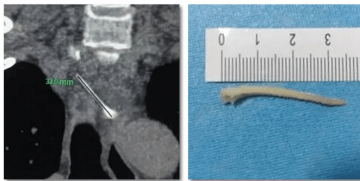

手术过程中,肖烨主任带领医务人员通过在患者十二指肠处插入一根柔软的管子,借助X光,发现患者的胆总管扩张,宽度大约有10毫米。在胆总管里,他们找到了一块直径约5毫米的小石头。为了取出这块结石,他们巧妙地切开了胆总管的开口处,然后使用一个8毫米宽的特殊气囊,像气球一样扩张开来,这样就能顺利地通过胆总管。接着,他们用一个取石球囊,像网兜一样把结石紧紧抓住并取了出来。结石取出后,他们还清理了胆道,以确保胆汁能够顺畅流动。最后,他们在患者的鼻子里放入了一根细管(鼻胆管),一直延伸到患者肝脏附近的胆管内,并连接着一个引流袋,帮助胆汁流出,确保胆汁不会倒流。X光显示,这根管子的位置准确。